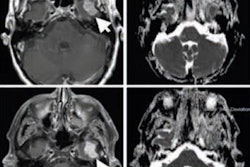

Steven Meikle, PhD, from the University of Sydney described just how far medical physics has come in the last 60 years. Looking first at the current state-of-the-art in cancer diagnostics, he explained how this involves anatomical imaging with CT, ultrasound, or MRI, plus PET/CT scans for staging. Treatment planning can be based on CT, MRI, or PET/CT, as can posttreatment imaging to monitor effectiveness. In 1956, only planar x-ray imaging was available. This was used for diagnosis, but not routinely for planning, while posttherapy monitoring relied solely on clinical observation.

Steven Meikle, PhD, from the University of Sydney examines the major advances that enabled the "medical physics revolution." Credit: Tami FreemanFor radiotherapy, treatment planning in 2016 uses model-based or Monte Carlo methods. Radiation is delivered via conformal techniques such as intensity-modulated radiotherapy (IMRT), image-guided radiotherapy (IGRT), volumetric-modulated arc therapy (VMAT), and stereotactic body radiotherapy (SBRT), using x-rays, electrons, photons, or ions. Verification is performed after, or even during, treatment delivery. In 1956, plans were hand-calculated based on anatomical landmarks and delivered using kilovoltage x-rays or high-energy gamma rays.

Meikle examined the major advances that enabled this "medical physics revolution." "In imaging, I nominate tomographic reconstruction as the single biggest advance that moved the field forward," he declared. Indeed, the significance of this development was recognized back in 1979, when Allan Cormack and Godfrey Hounsfield won the Nobel Prize in Physiology or Medicine for their development of computer-assisted tomography.

Brian Pogue, PhD, from Dartmouth discusses the evolution of diagnostic imaging. Credit: James DaceyPogue shared some example successes in medical imaging, such as low-dose CT, which was advanced by the development of new detectors, statistical modeling algorithms, iterative reconstruction, and patient-specific scans, as well as public awareness of need for low-dose scans. PET/CT and SPECT/CT, meanwhile, evolved thanks to hardware developments, improvements in reconstruction, and widespread adoption.

Another example is x-ray tomosynthesis for breast imaging, which was enabled by new detectors and sources, reconstruction algorithms, computer-aided detection (CAD) algorithms, and screening recommendations. Elsewhere, dual- and multienergy CT are now widely adopted, with the field in an exponential growth phase.

Then there's 3D ultrasound, which has benefited from faster digitization and 3D reconstruction techniques. "This might look like a technical curiosity, but its impact has been profound in both neonatal and breast cancer imaging," Pogue pointed out. Other success stories include MRI breast and prostate applications, surgical guidance and radiotherapy-positioning technologies, near-infrared spectroscopy, and robotic procedures.